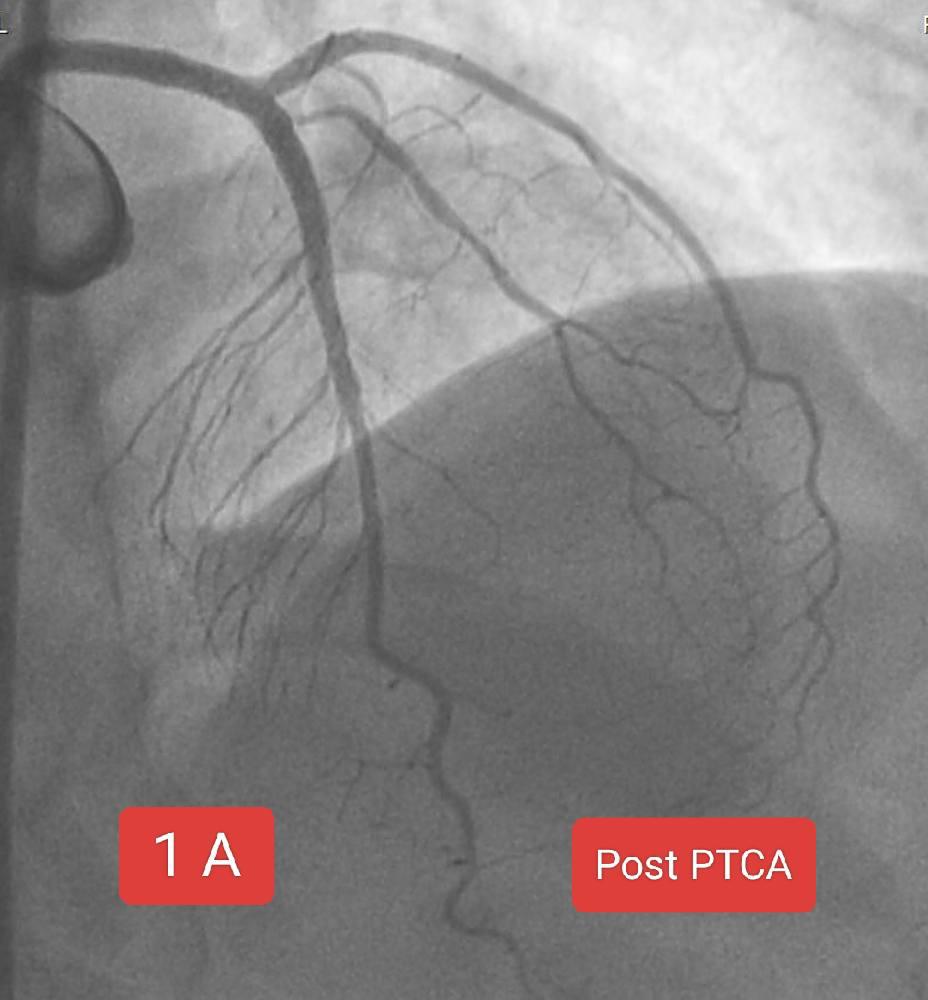

Two interesting cases of Left main stenting by mini crush technique done at Sunshine Hospital ,Bhubaneswar last month. Case 1 A 65 Years old Male Risk factors : Smoking, Hypertension Presented with Chest pain since 2 days ECG : Anterior wall STEMI ECHO : RWMA LAD Territory, LVEF 38% CAG : Left main + LAD + LCx disease PTCA done : Left main bifurcation stenting by Mini crush technique Case 1B 72 year old Male Risk factor : Smoking CAD Post PTCA status to OSTIOPROXIMAL LAD - D1 ( Bifurcation) ( 2020) Medications discontinued since 2022. ECG : aVR ST elevation ECHO : RWMA LAD Territory, LVEF : 45% CAG : Distal LMCA 95%, ostial LAD stent ISR 95% , ostial LCx 99% Patient refused CABG PTCA done : Left main bifurcation stenting by Mini crush technique Thanks to our cath lab team ( Sarfaraj Ahammed , Amit Gourav Bagh , Madhu Smita Swain , Anjan Jagannath Dash, Sanjib, Mami didi, Sameer and Raju) and Sunshine Hospital Bhubaneswar